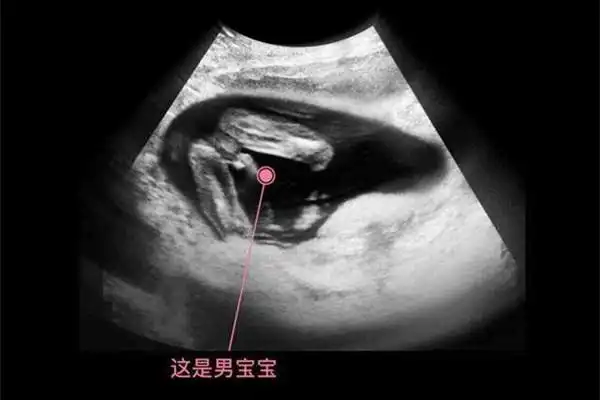

14周 2,在今天6.1儿童节,得知男宝一枚,接男_妈妈网孕育社区_妈妈网

一般来说胎儿14周左右,生殖器官就已经发育完全了.

怀孕14周b超看男女准确吗?